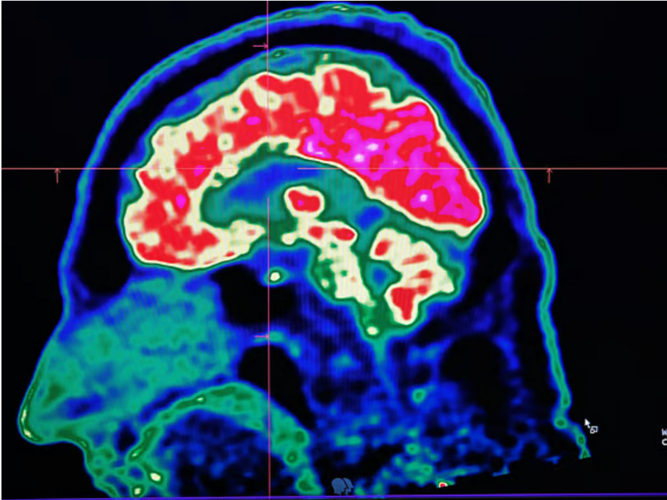

Alzheimer’s is a neurodegenerative disease that gradually damages memory and thinking skills. By the time symptoms such as memory loss appear, brain changes have often been underway for years.

Abnormal tau proteins can form tangled fibres in the brain, disrupting communication between nerve cells. Brain imaging tests can detect these tangles, and earlier research has suggested they may help predict symptom onset.